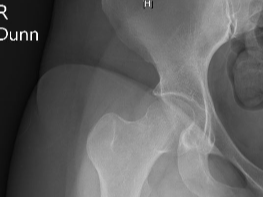

결국엔 뼈주사와 사타구니 인대에 프롤로주사도 맞았다.

내 엉덩이의 대상포진 자국을 보더니 프롤로로 변경.